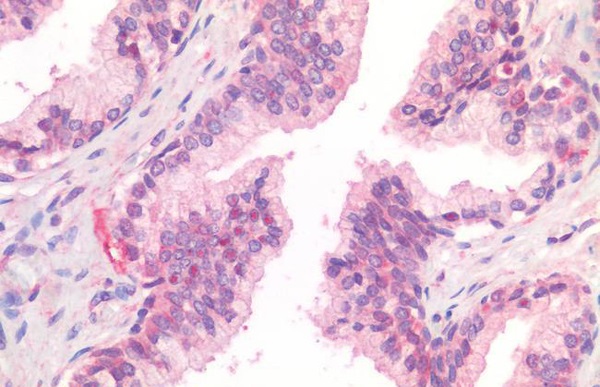

IHC (Immunohiostchemistry)

(Immunohistochemistry of paraffin-embedded Human thyroid cancer tissue using TEAD3 Polyclonal Antibody at dilution of 1:50(×200))